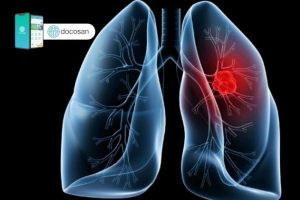

Ung thư phổi giai đoạn đầu làm sao nhận biết?

Ung thư phổi giai đoạn đầu cần được chẩn đoán, điều trị sớm thì kết quả điều trị sẽ tốt hơn, cải thiện tiên lượng sống còn của bệnh nhân. Tuy nhiên, bệnh nhân khi được chẩn đoán ung thư phổi đều đã ở giai đoạn muộn. Bài viết dưới đây của Doctor có sẵn […]